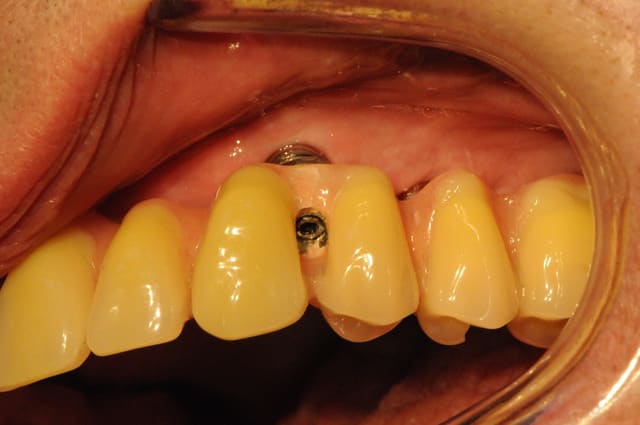

haaa bein voilà...fallait bien que çà arrive un jour...ptit cas tout chaud de cet aprèm...

faut dire que çà fait 2 ans que je ne l'ai pas vue...zéro pointé de maintenance...

hygiène bof...je l'avais pourtant prévenue!!!

l'implant en 22 va bien, l'image est bizarre du fait de son angulation...et s'il parait bien gros...c'est qu'il est bien gros (un 4.7/16!!!) car posé en EII et la racine de la 22 était énorme...

en 44/45 tout va bien, 34 lui aussi, 36 pas trop mal....mais 35!!!

bizarre quand même, j'ai sondé, pas de perte en lingual mais perte de 3mm en vestibulaire...

je l'ai mise sous AB, fait un bon nettoyage/aéropolissage, dit de bien reprendre l'hygiène, et rdv pour contrôle dans un mois...